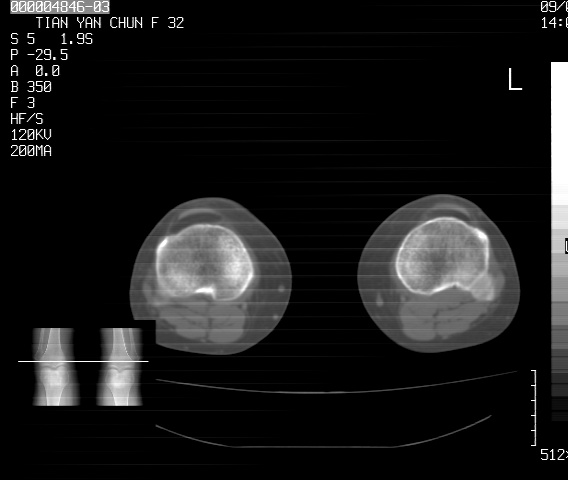

标题: CT18487:请会诊,女32岁,左膝疼痛数日 [打印本页]

标题: CT18487:请会诊,女32岁,左膝疼痛数日

关节面软骨有硬化环考虑退行性变

定位片可见髁间棘骨质增生,支持膝关节退行性变。

定位片可见髁间棘骨质增生,支持膝关节退行性变。建议mri 检查

考虑骨性关节炎